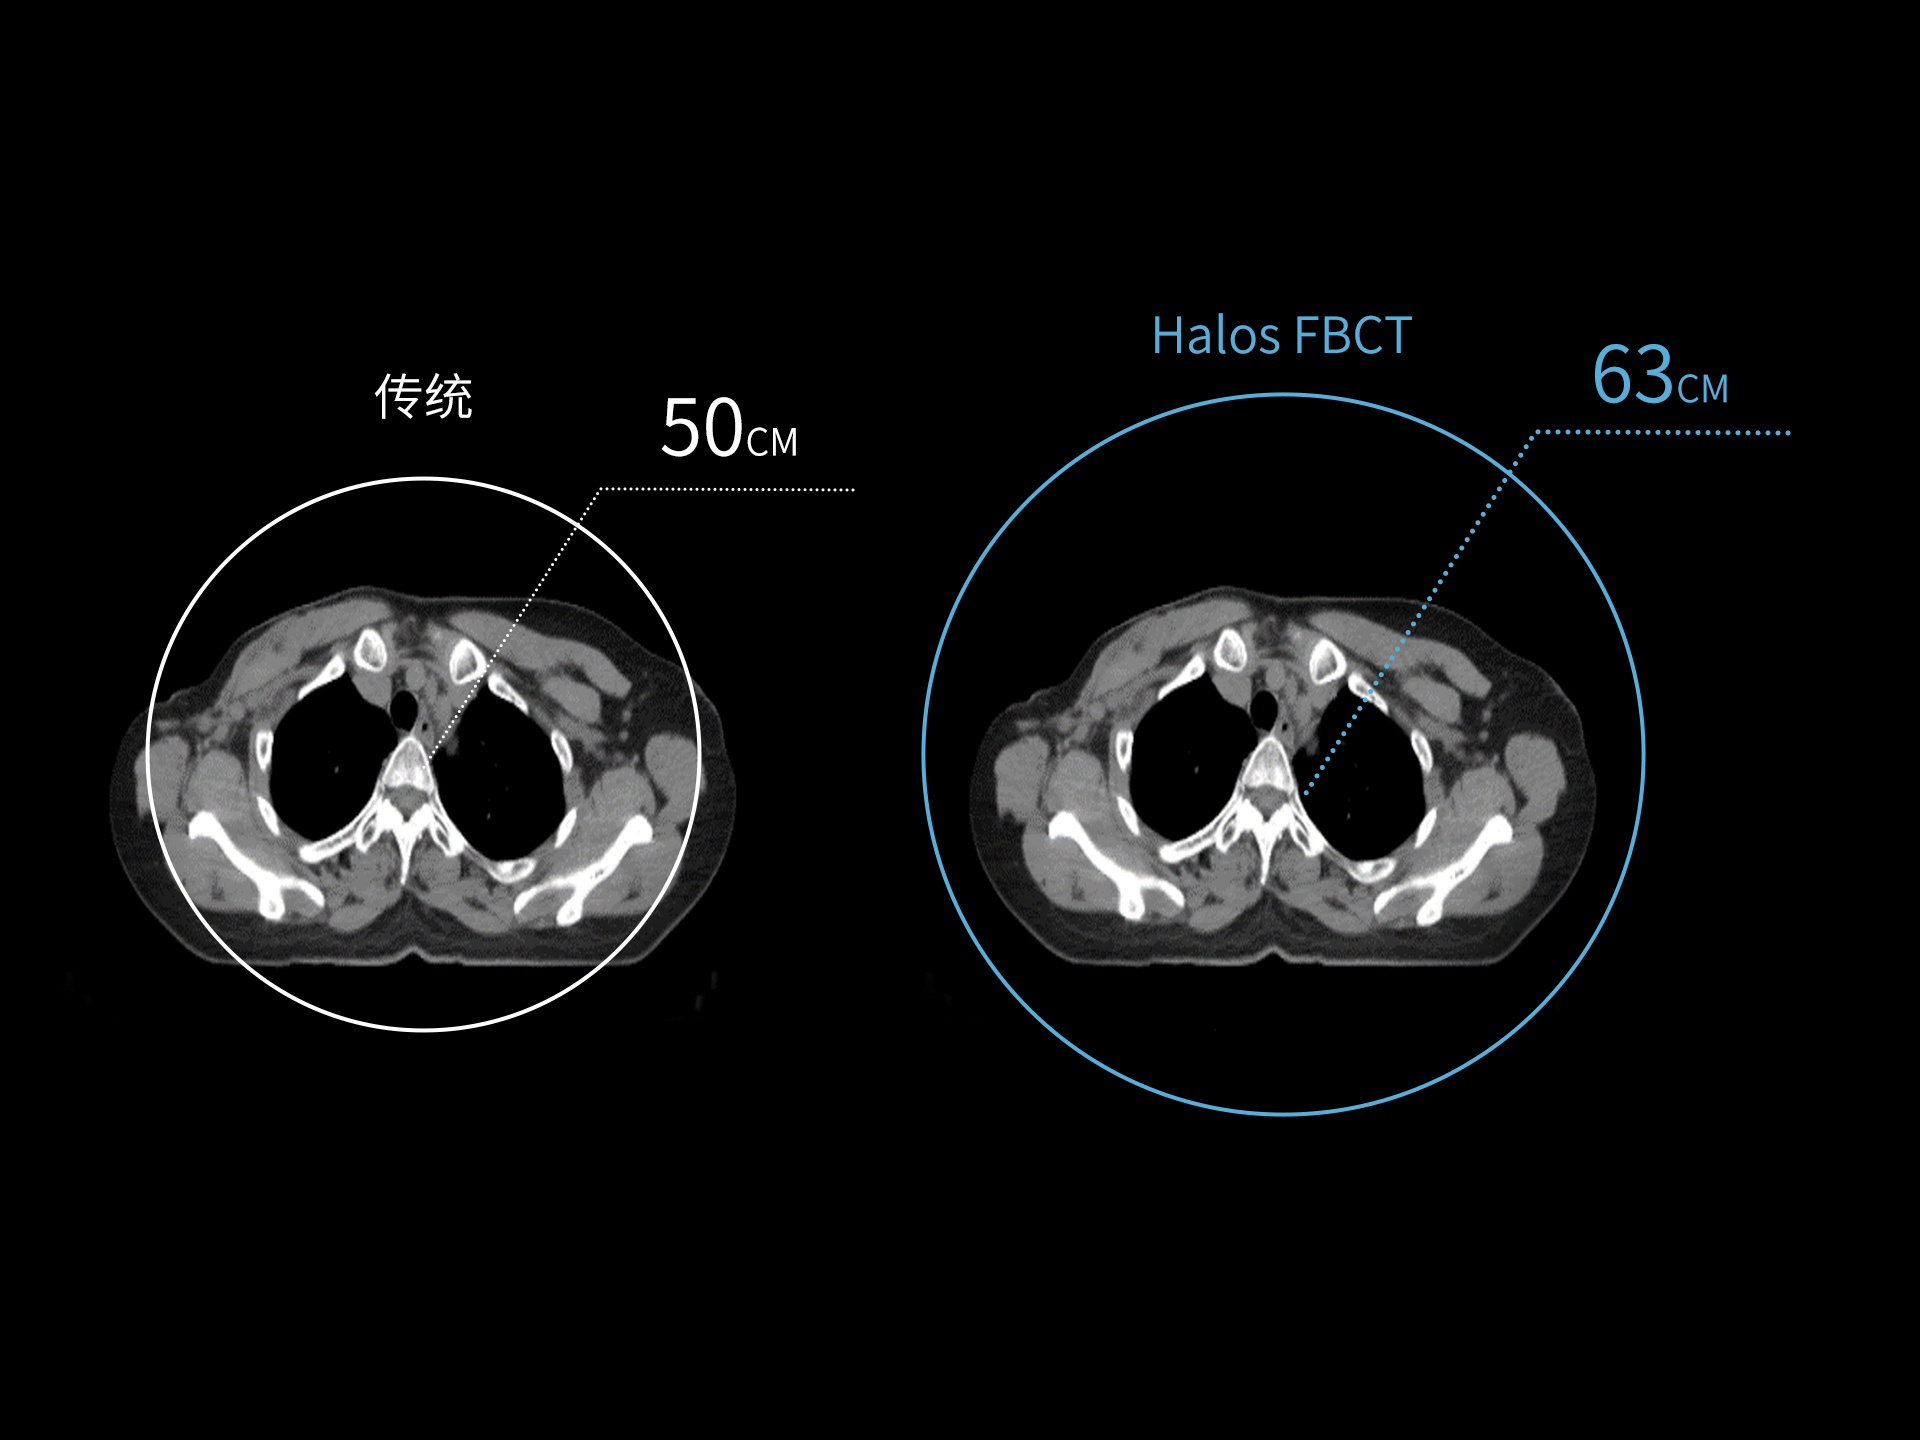

uLinac HalosTx®搭载新一代 87cm 大孔径诊断级CT图像引导系统,全能进阶,实现高清图像质量和全景视野的完美平衡,开辟全疗程 「影像感知」 ,为临床提供更自信、更全面的临床依据。

扇形束成像,极低散射,媲美CT-sim的影像品质

3mm @ 0.3% 高软组织对比度,0.55mm薄层扫描,精确鉴别肿瘤靶区边界

全疗程肿瘤变化感知,加速高清影像引导高水平普及

精准CT值,完美满足勾画、剂量计算要求

从数据源头提升图像质量,高清呈现细微变化,全面精进机载影像实力

提供传统 的CT 模拟机所一致的HU值精度(±10HU)

87cm CT影像孔径设计适配多种摆位姿势,兼顾不同体型患者

标准视野 63cm,避免扫描信息缺失

轴向视野 91cm,轻松实现长靶区扫描

0.37s/360° 旋转速度,减少运动伪影,大幅提高时间分辨率

4D CT 动态肿瘤追踪,运动靶区精准勾画

低剂量CT,保证成像质量的同时降低患者辐射剂量